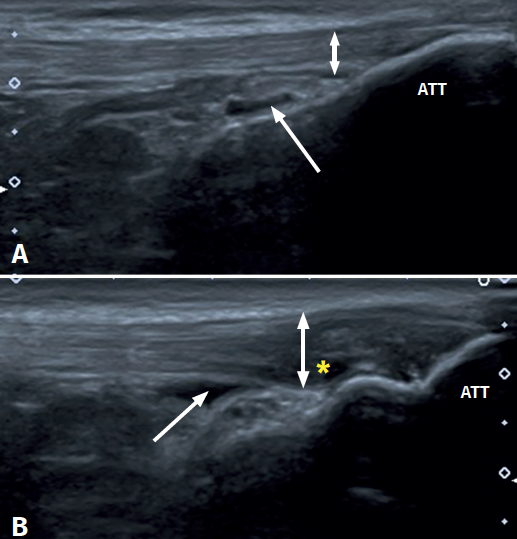

Figure 1. Ultrasound images (linear probe) of the patellar tendon, distal portion. Longitudinal view of the tendon fibres at insertion in the anterior tibial tuberosity (ATT). A: distal insertion of the normal patellar tendon. The arrow shows mild bursitis, and the double arrow indicates the normal size of the tendon; B: distal patellar tendinopathy showing the deep infrapatellar bursa (arrow) containing fluid (hypoechoic image), with increased tendon thickness (double arrow) and a fibrillar pattern showing decreased echogenicity (hypoechoic) secondary to disruption of the collagen bands (asterisk).

Distal PT in the adult (Figure 1) is also found as a complication of Osgood-Schlatter disease. This form of osteochondritis of the anterior tibial tuberosity manifests at prepubertal ages (males: 12-15 years; females: 8-13 years), it is produced by traction of the tendon upon its distal insertion in the distal tuberosity of the tibia, and is characterised by pain in response to palpation of the anterior tibial tuberosity in the physical examination(13). Its appearance has also been described at 12-18 months, before the completion of skeletal maturation(14).